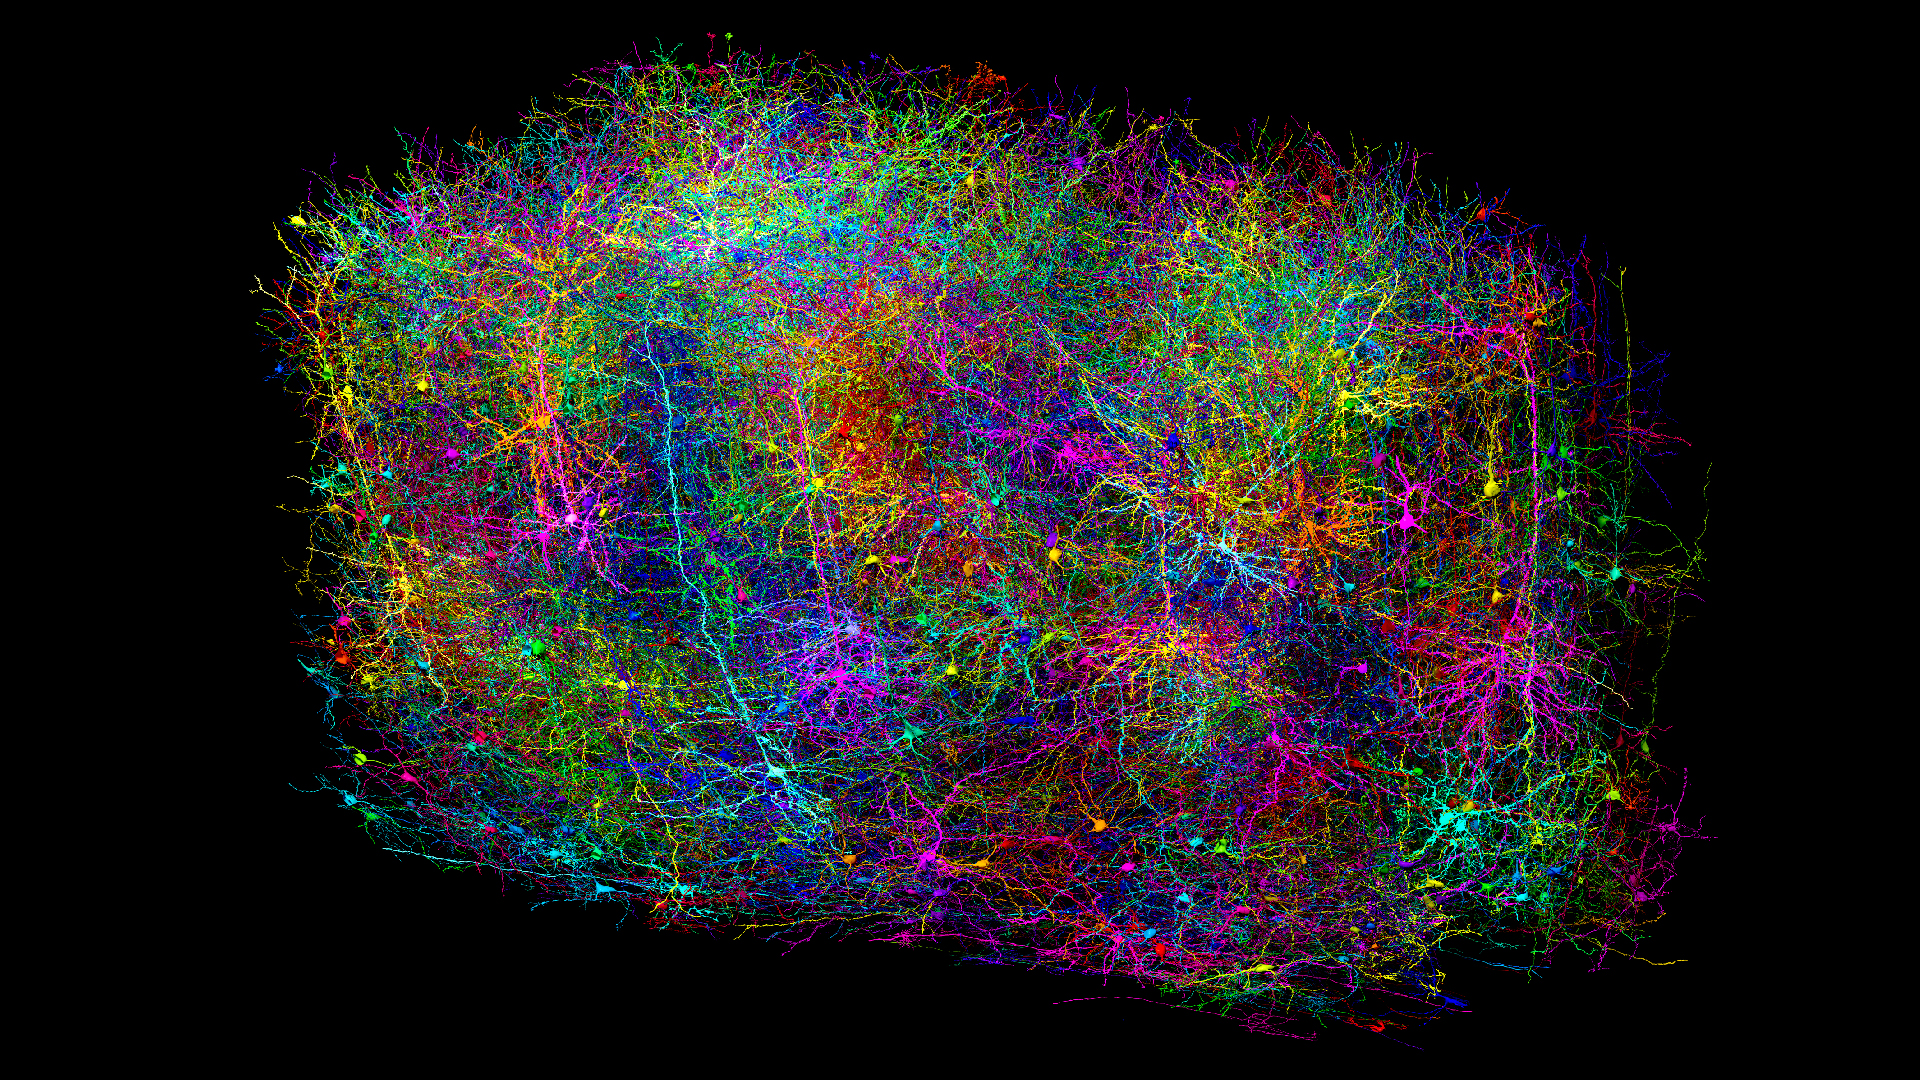

Thirty-one of the participants also had their brains scanned by functional magnetic resonance imaging (fMRI) while they took part in another social-rejection experiment. Each subject was told he or she would be playing a ball-tossing computer game with two other participants. In fact, the two other participants were not volunteers, but computer-generated "players."

In the fMRI scanner, subjects saw a computer screen with a virtual hand to represent themselves and two cartoon characters representing the other two "participants." In the first round of the game, the subject received the ball and could toss it back and forth with the other players. In the second round, the subject never received the ball, and so experienced social rejection.

The researchers examined activity in two brain regions, the dorsal anterior cingulated cortex and the anterior insula. They compared the activity in these regions when the subject was included in the game to the activity when the subject was excluded. The greater the difference, the more sensitive the subject was to social rejection.